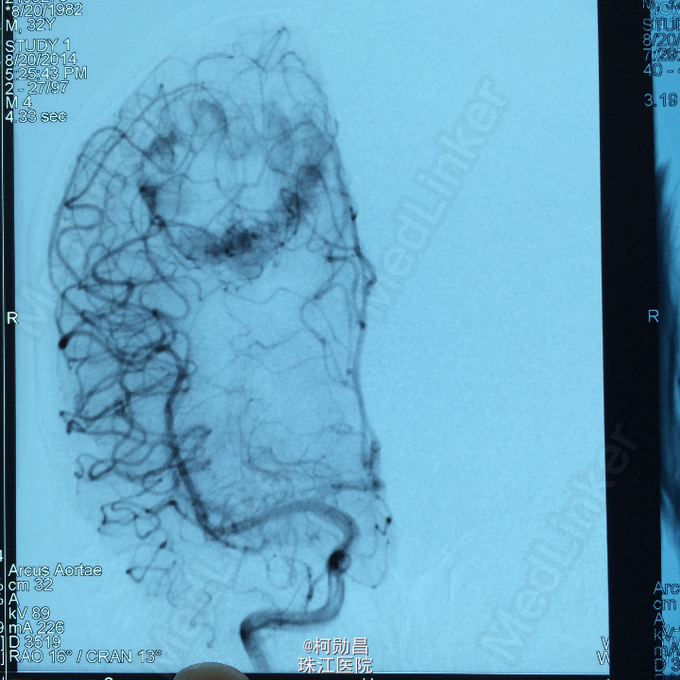

主诉:头痛伴右上肢麻木无力两个月,加重七天 病史:两个月前出现头痛,走路不稳,右上肢无力,不能持物,过去两个月曾有两次癫痫全面发作,发作时意识丧失,但无尿失禁及舌头咬伤。查头MRI示右侧顶叶占位,考虑脑膜瘤。

查体:巴氏征阳性,左侧肢体感觉减退,肌力正常,余无特殊阳性。 辅助检查:查头MRI示右侧顶叶占位,考虑脑膜瘤。

诊断:左侧顶叶占位 处理:行DSA检查,提示肿瘤染色,予PVA颗粒行血管内栓塞治疗。

术后再予开颅手术治疗,书中见供血动脉闭塞,出血量少。